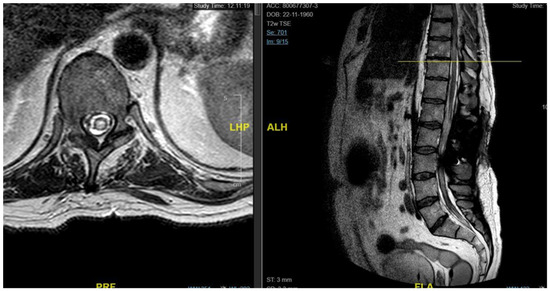

3.4.5. Case 5

| Patient | 1 | 2 | 3 | 4 | 5 |

|---|---|---|---|---|---|

| Age | 46 | 48 | 62 | 43 | 68 |

| Gender | M | M | M | F | F |

| Level | T12–L2 | C5–C6 | T7–T10 | T8–T9 | T8–T11 |

| Location | Intramedullary | Intradural | Intradural–Extradural | Intramedullary | Intradural |

| Primary/secondary | Secondary | Secondary | Secondary | Secondary | Secondary |

| Numbness | Yes | No | Yes | Yes | Yes |

| Gait disturbances/ataxia | No | Yes | No | Yes | Yes |

| Lumbar pain | No | No | Yes | Yes | No |

| Urinary–bowel dysfunction | Yes | No | Yes | No | No |

| Limb weakness | Yes | Yes | No | No | No |

| Paraplegia | No | No | Yes | No | No |

| Sexual disfunction | Yes | No | No | No | No |

| Surgical treatment | lysis of adherences and syrinx cavity opening | resection of the cystic formation and adhesiolysis | resection of the cystic formation and adhesiolysis | resection of the cystic formation and adhesiolysis | resection of the cystic formation and adhesiolysis |

| Complications | CSF fistula | infection | None | CSF fistula | None |

| KPS pre-op (%) | 70 | 50 | 70 | 80 | 90 |

| KPS post-op (%) | 80 | 50 | 60 | 90 | 80 |

| ASIA score pre-op | C | B | B | C | D |

| ASIA score post-op | D | B | C | C | D |

| Follow-up (years) | 2 | 2 | 2 | 3 | 1 |